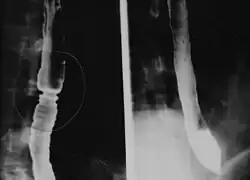

Radiologically, the term "ringed esophagus" has been used for the appearance of eosinophilic esophagitis on barium swallow studies to contrast with the appearance of transient transverse folds sometimes seen with esophageal reflux (termed "feline esophagus").[12]

Endoscopically, ridges, furrows, or rings may be seen in the esophageal wall. Sometimes, multiple rings may occur in the esophagus, leading to the term "corrugated esophagus" or "feline esophagus" due to the similarity of the rings to the cat esophagus. The presence of white exudates in the esophagus also suggests the diagnosis.[13] On biopsy taken at the time of endoscopy, numerous eosinophils can be seen in the superficial epithelium. A minimum of 15 eosinophils per high-power field are required to make the diagnosis. Eosinophilic inflammation is not limited to the esophagus alone and does extend through the whole gastrointestinal tract. Profoundly degranulated eosinophils may also be present, as may micro-abscesses and an expansion of the basal layer.[3][10]